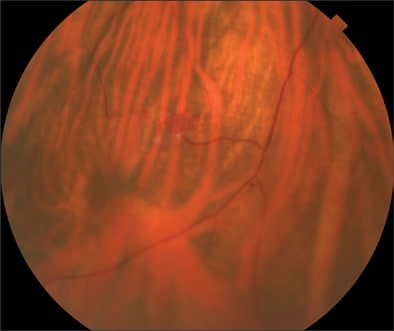

Ophthalmologic examination demonstrated a corrected visual acuity of 20/20 in each eye and the patient correctly identified 11/11 Ishihara color plates. Pupils were briskly reactive without any afferent defect. Slit-lamp examination of the anterior segment was unremarkable. Dilated funduscopic examination showed 3 midperipheral endophytic retinal hemangiomas in the right eye and 1 peripheral hemangioma in the left eye. Fluorescein angiography confirmed the presence of these retinal hemangiomas.

Figure 3. Midperipheral endophytic retinal hemangiomas in the right eye.

Figure 4. Another view of midperipheral endophytic retinal hemangiomas in the right eye.